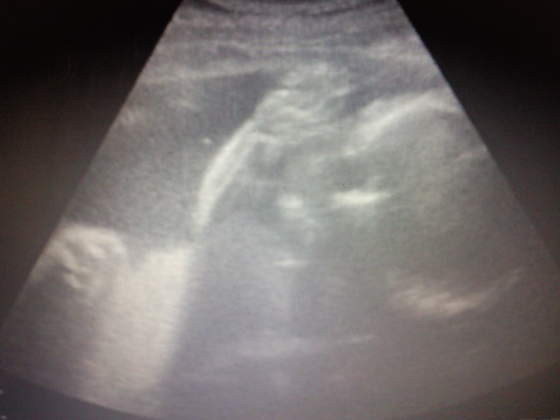

Nasze fasolki na USG

Zdj&#281;cie1257..jpgZdj&#281;cie1264..jpgZdj&#281;cie1258..jpg

a to nasz córcia w 27 tyg jakie ma sliczne usteczka:-D:-D:-D